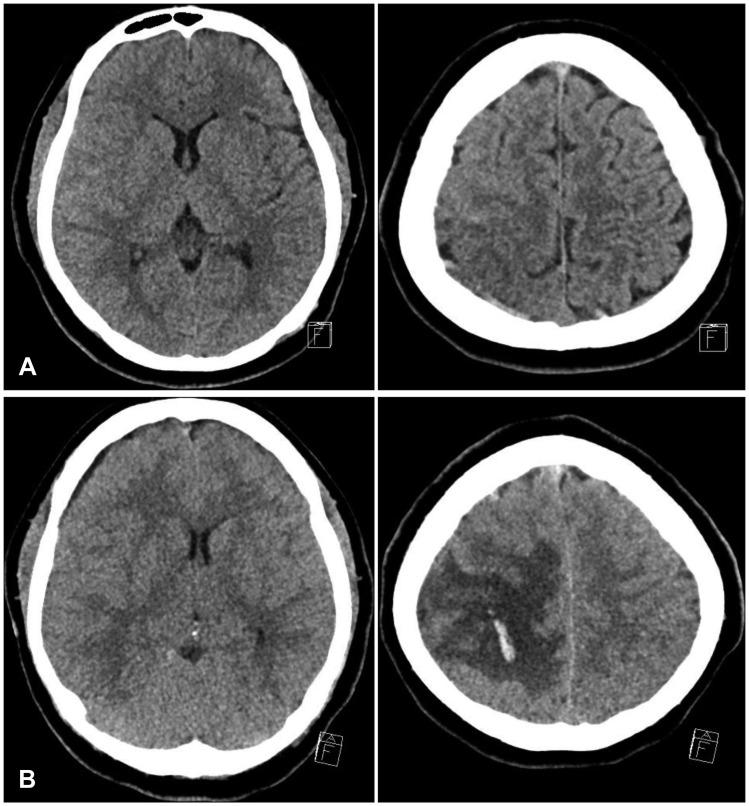

脑静脉窦血栓形成(CVST)是一种罕见疾病。早期诊断和治疗很重要,因为CVST有潜在致命风险。妊娠和产褥期是已知的CVST危险因素。在此,我们报告一例患者在正常阴道分娩后发生上矢状窦血栓形成的病例。一名20岁女性在正常阴道分娩两天后出现头痛和癫痫发作。最初,脑部计算机断层扫描(CT)显示右侧顶叶和外侧裂蛛网膜下腔出血,伴有轻度脑水肿。CT血管造影显示上矢状窦血栓形成。在弥散加权磁共振图像上可见多处微梗死。立即给予静脉输注肝素和甘露醇。治疗开始两天后,患者突然出现神经功能恶化,伴有左侧偏瘫。脑部CT显示中度脑水肿和出血密度影。进行了急诊减压颅骨切除术,并在术后第1天重新给予肝素。术后第9天,患者的精神状态从昏迷改善为嗜睡,但左侧偏瘫仍然存在。CT血管造影显示上矢状窦血栓形成有所减轻。上矢状窦血栓形成是分娩后一种罕见的并发症,预后不良。及时诊断和治疗对于预防神经功能恶化很重要。